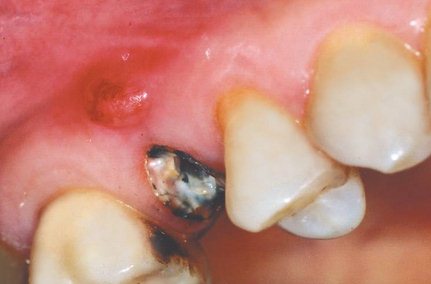

Хронический периодонтит сопровождается заметным повышением подвижности зубов, изменяется их положение, образуются межзубные щели. Кровоточивость десен может возникать даже без механического воздействия на них. Наблюдается систематическое выделение гноя, абсцессы и острая боль.

Хронический периодонтит характерен своей периодичностью – обострение периодонтита сменяется затиханием процесса, и больной в эти периоды может успокаиваться, в очередной раз, откладывая посещение врача. В периоды, когда происходит обострение периодонтита, десна краснеет и опухает, зубная боль постоянна и усиливается от прикосновения к зубу. Наблюдается повышение температуры тела.

Обострение периодонтита требует хирургических методов с целью удаления гнойного содержимого. Это препятствует некрозу тканей, распространению воспаления, ликвидирует или ослабляет боль. После удаления гноя врач начинает лечение периодонтита.